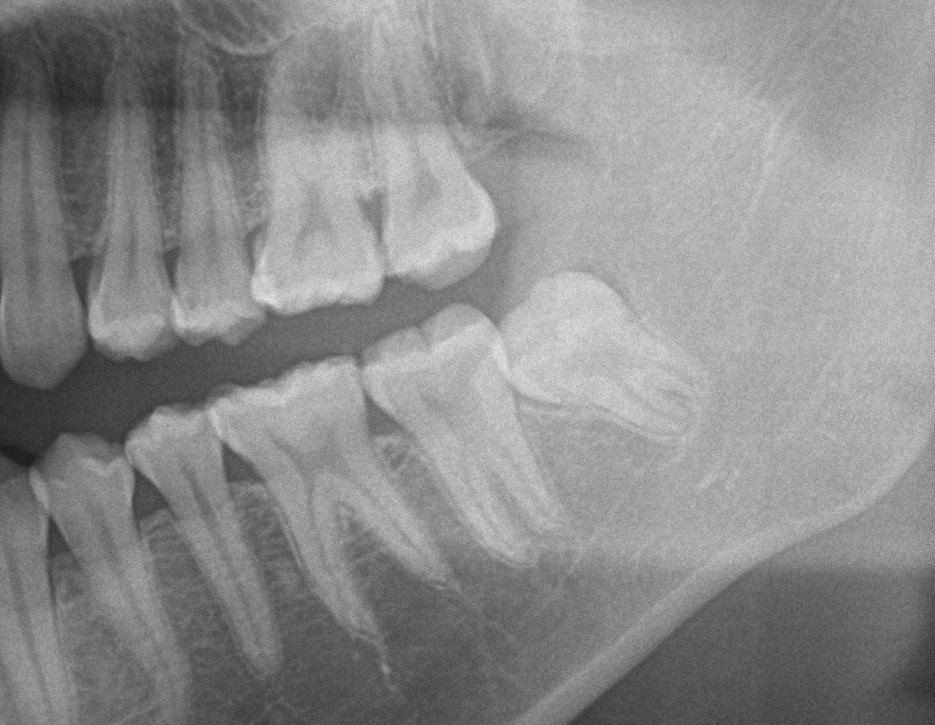

以下の二つの完全に埋まってる親知らず簡単に抜けます。